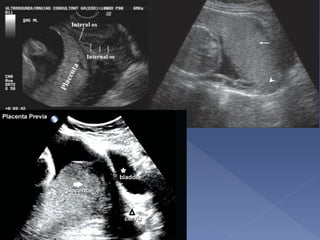

 Anterior/Posterior/Lateral/Fundal

 Placenta Previa

› Marginal

› Partial

› Complete

 Low-Lying

Midline sagittal scan at 28 weeks shows the posterior

placenta (P) completely covering the cervix (C). B,

maternal bladder

the placenta had invaded

through the myometrium to

the bladder wall